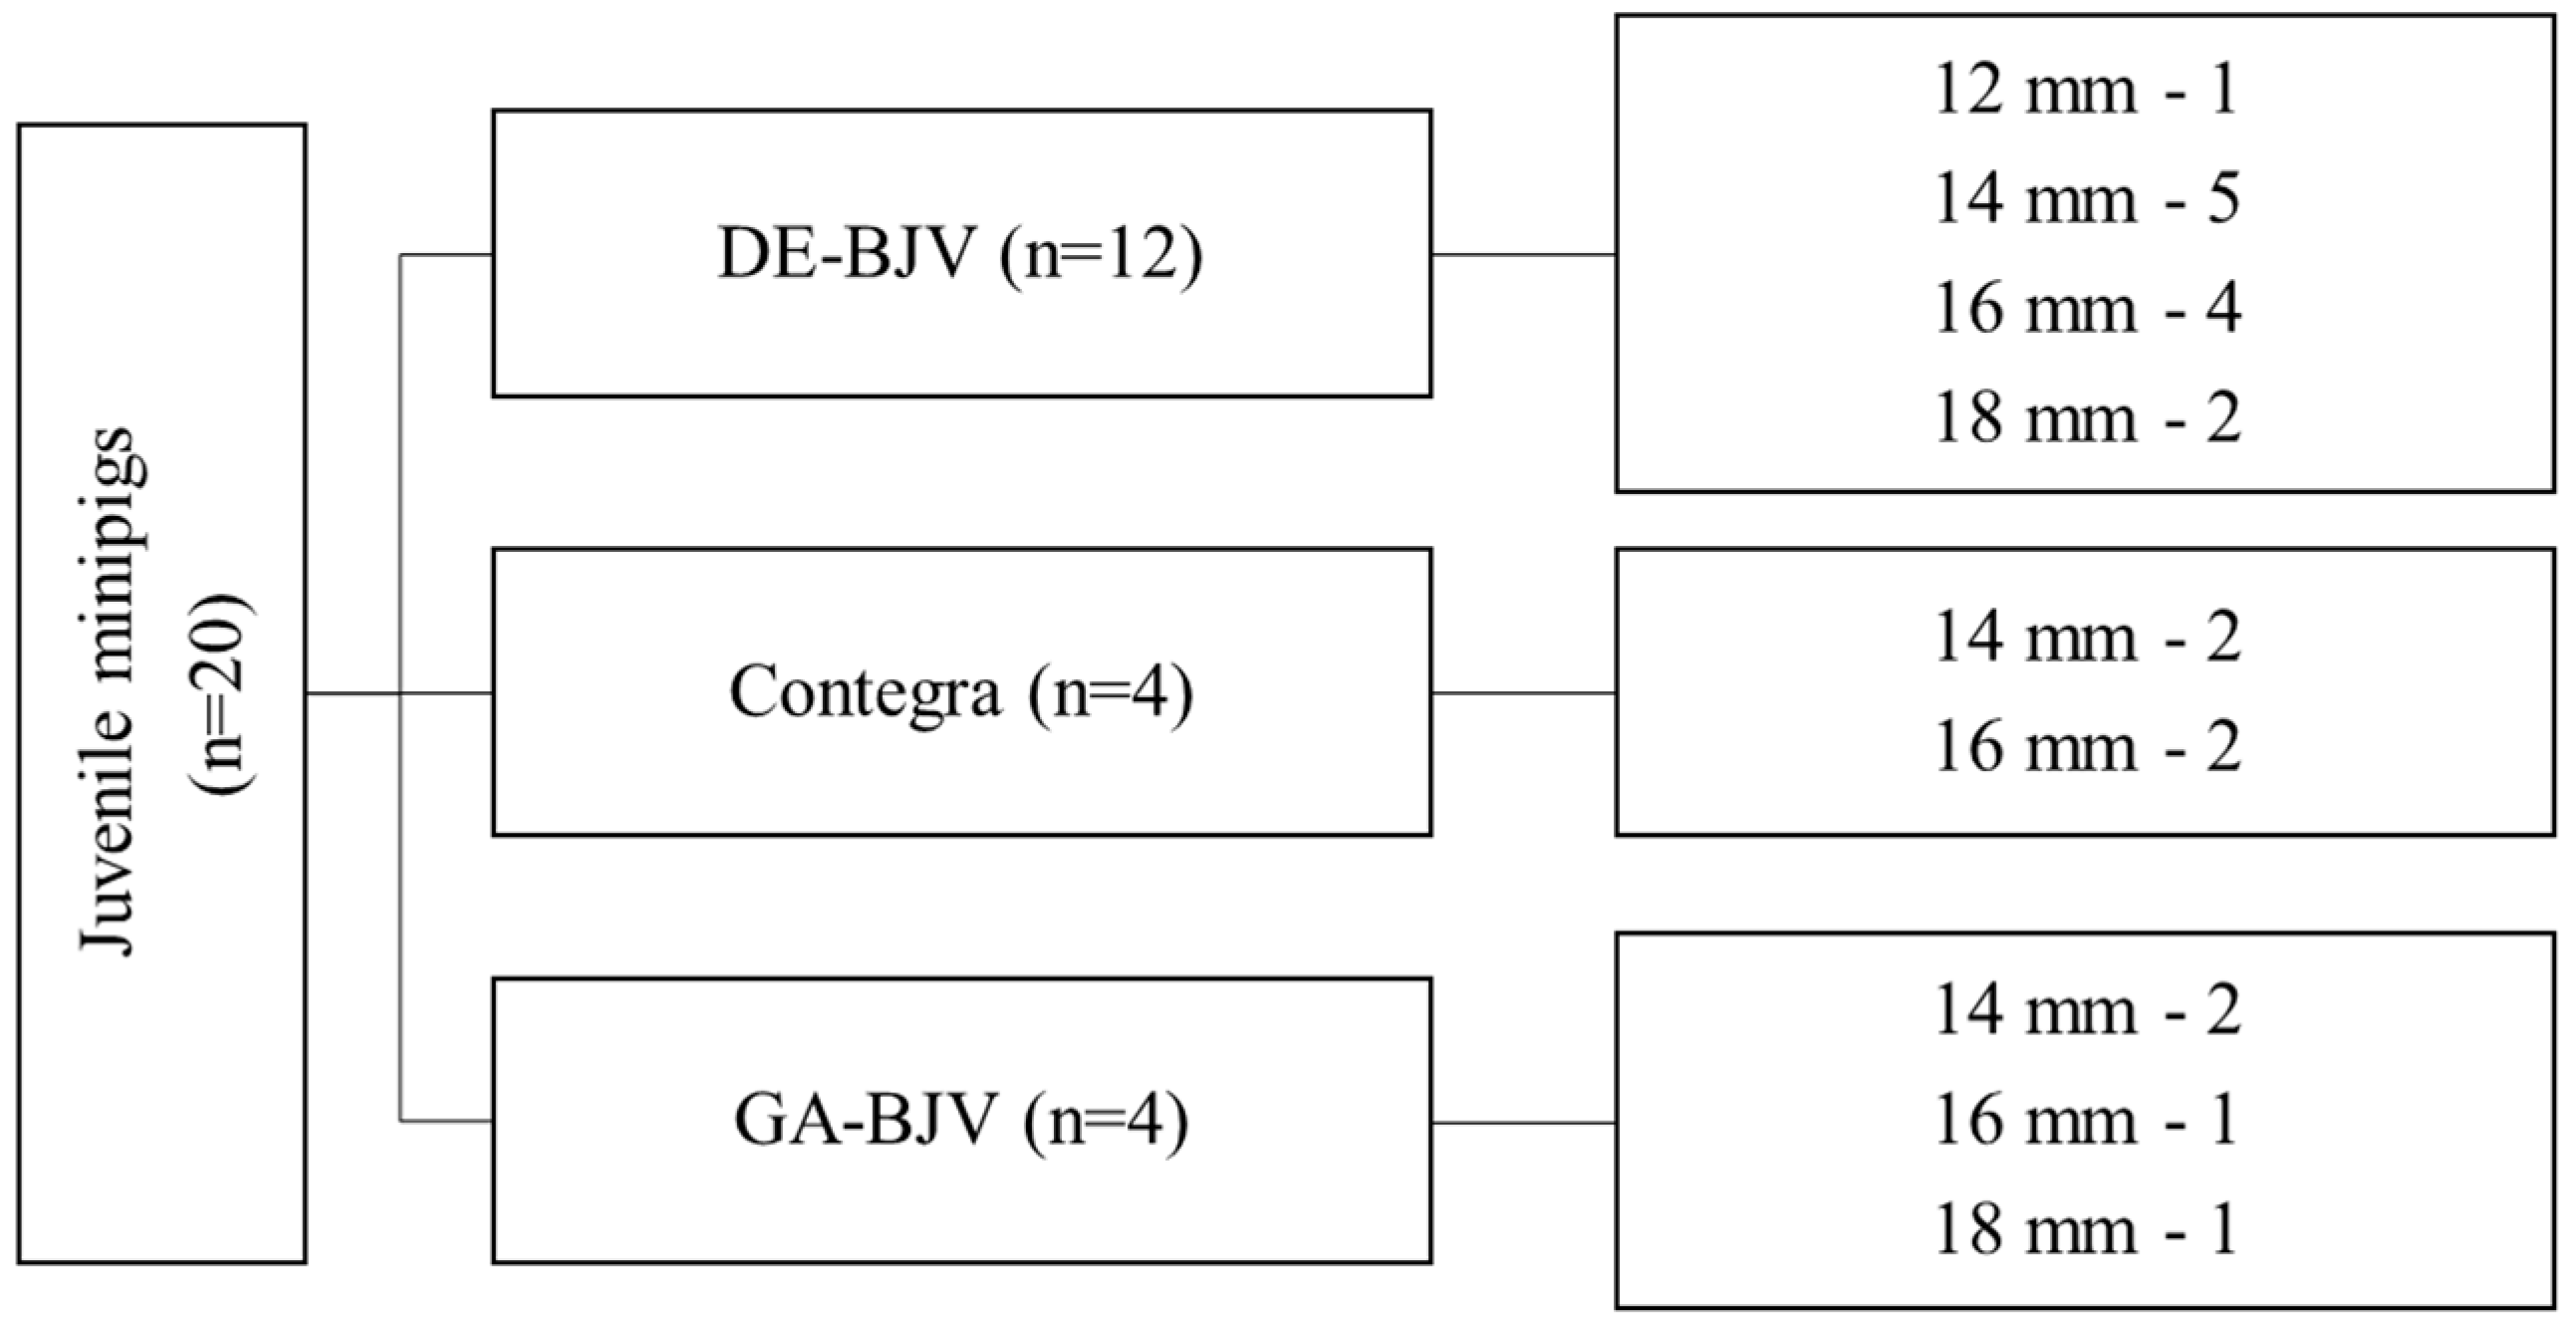

2.1. Study Design